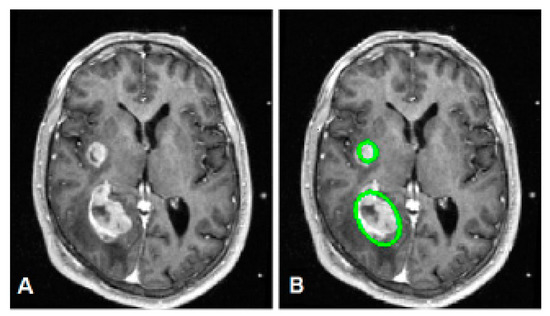

4. Experimental Results

Convergence Issue of the Proposed Model